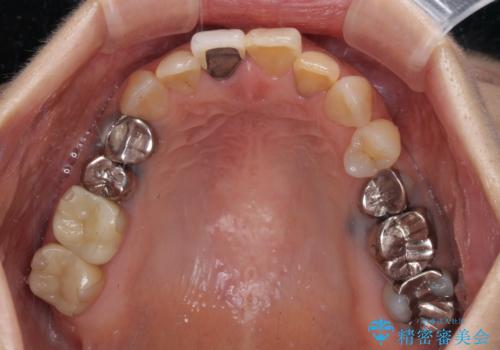

- 近医にて奥歯の抜歯が必要と言われたとのことで来院された患者様です。

診断の結果、奥歯は歯根が破折しており、抜歯が必要な状況でした。

インプラントあるいはブリッジによる補綴治療が考えられましたが、前後の歯が大きな銀歯であったため、オールセラミックブリッジにより3本の歯を審美的に仕上げることとしました。

前歯は神経を取り除いて変色した歯や金属の縁が見える歯などがあり審美的に気になっていましたが、治療するかどうかは悩んでいらっしゃいました。

ところが、奥歯の治療を開始する前に、神経が失活して根尖部に病変のある前歯が著しく痛み出したため、根管治療を行うこととなりました。